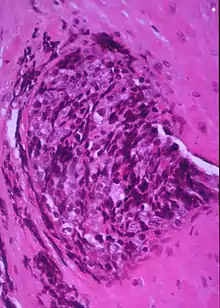

ورم الخلية المستديرة الزرقاء الصغيرة (بالإنجليزية: Small-blue-round-cell tumor) ويُدعى اختصاراً SBRCT وقد يُسمى أيضاً ورم الخلية الصغيرة المستديرة (بالإنجليزية: Small-round-cell tumour) ويُدعى اختصاراً SRCT، هو مُصطلح في علم أمراض الأنسجة يُقصد فيه أي فرد من أعضاء مجموعة الأورام الخبيثة التي تمتلك مَظهر مُميز تحت المجهر، أي أنها تتكون من خلايا صغيرة مدورة تُصبغ باللون الأزرق عند استعمال صبغة الهيماتوكسيلين واليوزين الروتينية.[1]

تكاثف بطانة الرحم السدوية يُحاكي ورم الخلية المستديرة الزرقاء الصغيرة.

تكاثف بطانة الرحم السدوية قد يُحاكي ورم الخلية المستديرة الزرقاء الصغيرة.